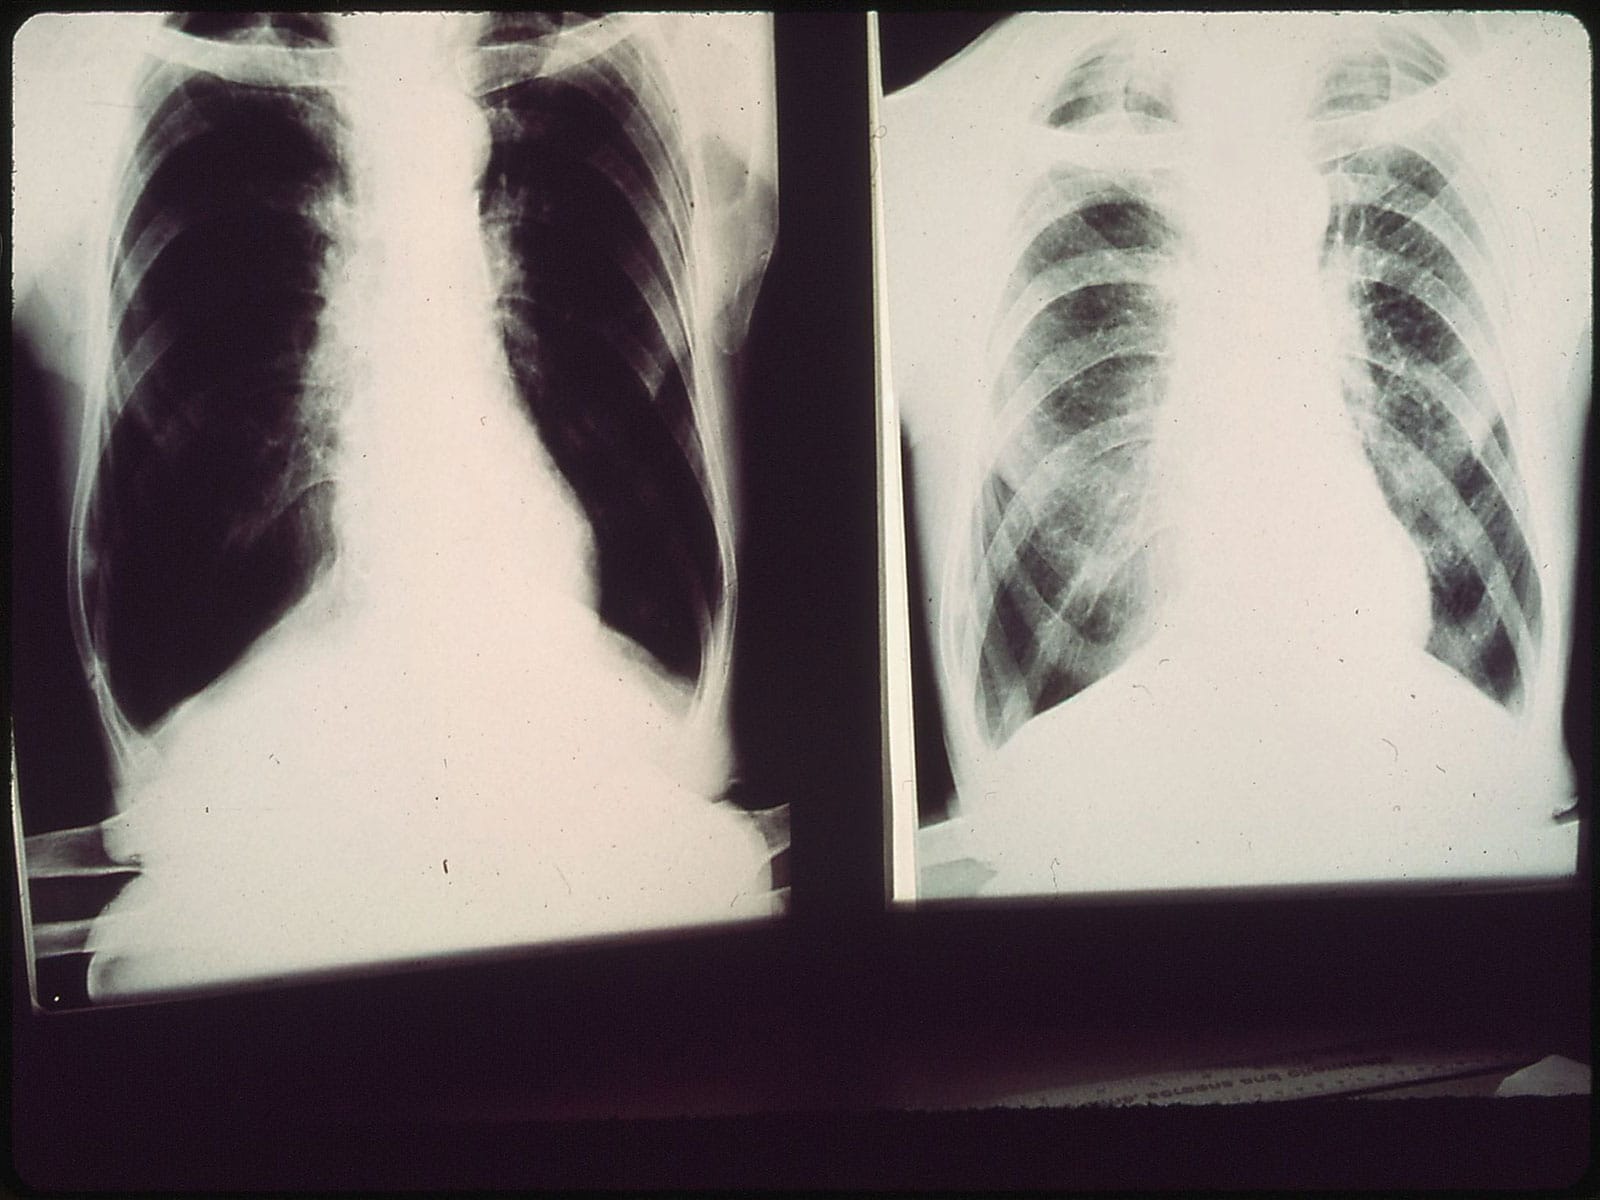

Testiranje će se održati u okviru Svetskog dana borbe protiv hronične opstruktivne bolesti pluća (HOBP) pod sloganom “Nije prekasno” kako bi se edukacijom stanovništva povećala svest o prevenciji i pravilnom lečenju ove bolesti.

HOBP se uglavnom javlja kao posledica dugogodišnjeg pušenja, a veliki broj ljudi nije ni svestan da je već oboleo.

Bolest se razvija polako, tokom više godina, čak i decenija, a odlikuju je otežano disanje, zamaranje pri obavljanju uobičajenih aktivnosti, hronični kašalj – navode u Zavodu.

Simptomi hronične opstruktivne bolesti pluća, kako navode, mogu biti kašalj koji ne prolazi, iskašljavanje šlajma i sluzi, ostajanje bez daha i zamaranje pri svakodnevnim i jednostavnim fizičkim aktivnostima kao što su penjanje uz stepenice, šetnja, odlazak u kupovinu, kupanje i oblačenje.